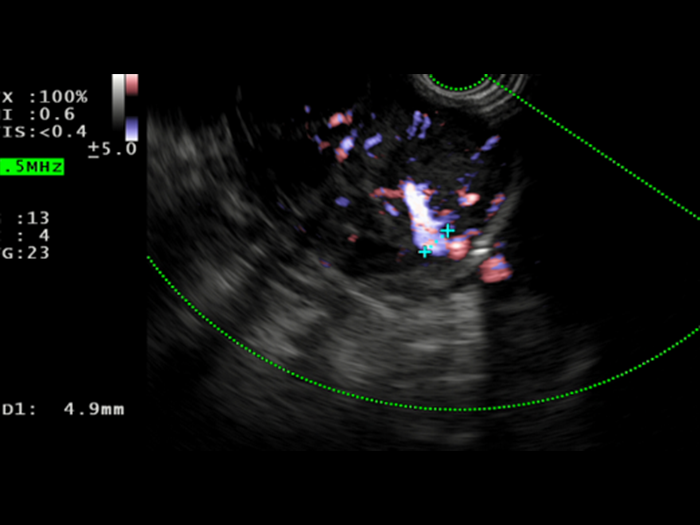

Saul was consented to move forward with an EUS-guided FNB, that was performed with Acquire™ S. This allowed his gastroenterologist to further assess the lesion. A 51.9 x 47.9 mm hypoechoic, inhomogeneous lesion, which appears hypervascularised on Hi Flow, is observed. Unfortunately, an advanced, unresectable GIST is still suspected.​